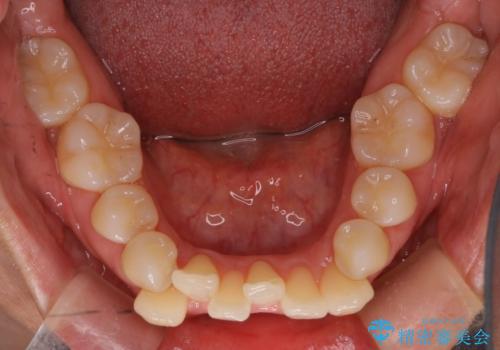

【抜歯ケース】前歯のガタガタをインビザラインで治療

- 前歯のガタガタを主訴に来院されました。

抜歯が必要なケースでしたが、インビザラインでの治療を希望されワイヤーを使用せずに治療を完了しております。

抜歯を伴う矯正治療はマウスピース矯正よりもワイヤー矯正の方がメリットが多いです。当院で抜歯を伴うマウスピース矯正を希望される場合は、場合によってワイヤーを使うことを了承していただいた上で治療を行なっています。